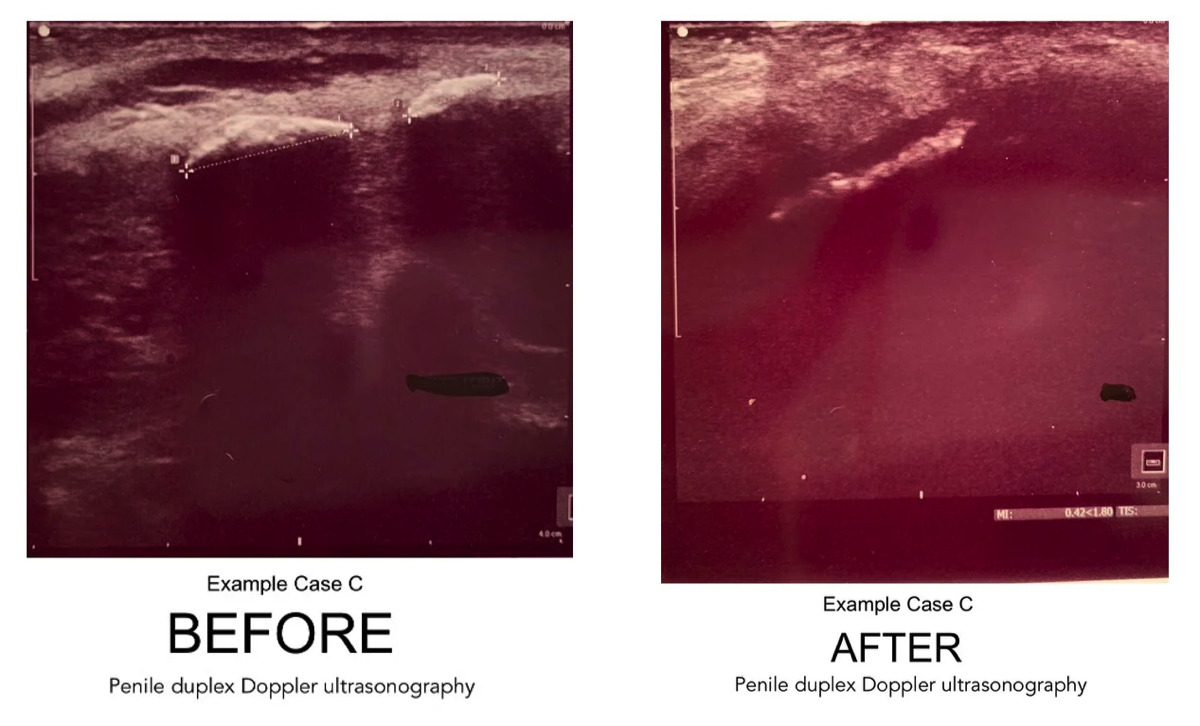

Highlights: Calcified Plaque Before & After Sonogram Images

Following is a set of four "before and after" duplex sonogram images of Peyronie's patients with calcified plaques